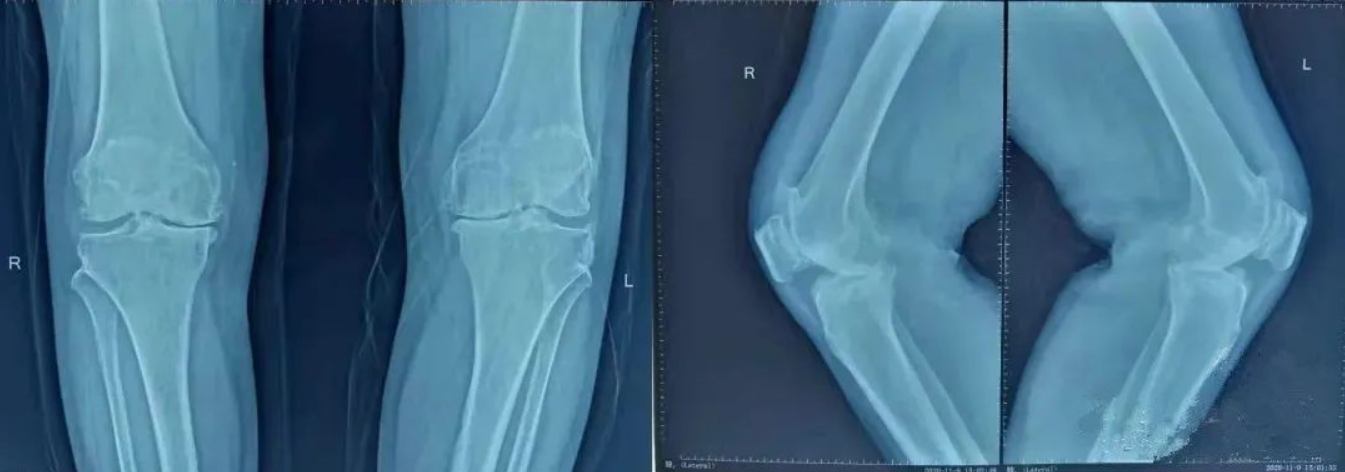

患者女性,61歲,主因“雙膝關節疼痛,活動受限10年余”入院。患者于10年余前無明顯誘因出現雙膝關節疼痛,活動受限,活動后癥狀加重,休息后癥狀可緩解。于當地醫院行關節腔注射玻璃酸鈉等對癥治療后癥狀緩解不明顯。現患者為求進一步診治,遂來我科就診。雙膝關節呈輕度內翻畸形,雙膝關節處未查及明顯壓痛。膝關節活動度:左:屈曲90°,伸直:-5°,右:屈曲90°,伸直:-10°。雙膝關節抽屜試驗,側方應力試驗,半月板旋轉擠壓試驗陰性。雙下肢未查及明顯感覺減退,雙側足背動脈搏動可觸及。

雙側膝關節內側間隙變窄,邊緣骨贅形成,軟骨下骨硬化,關節呈屈曲內翻畸形